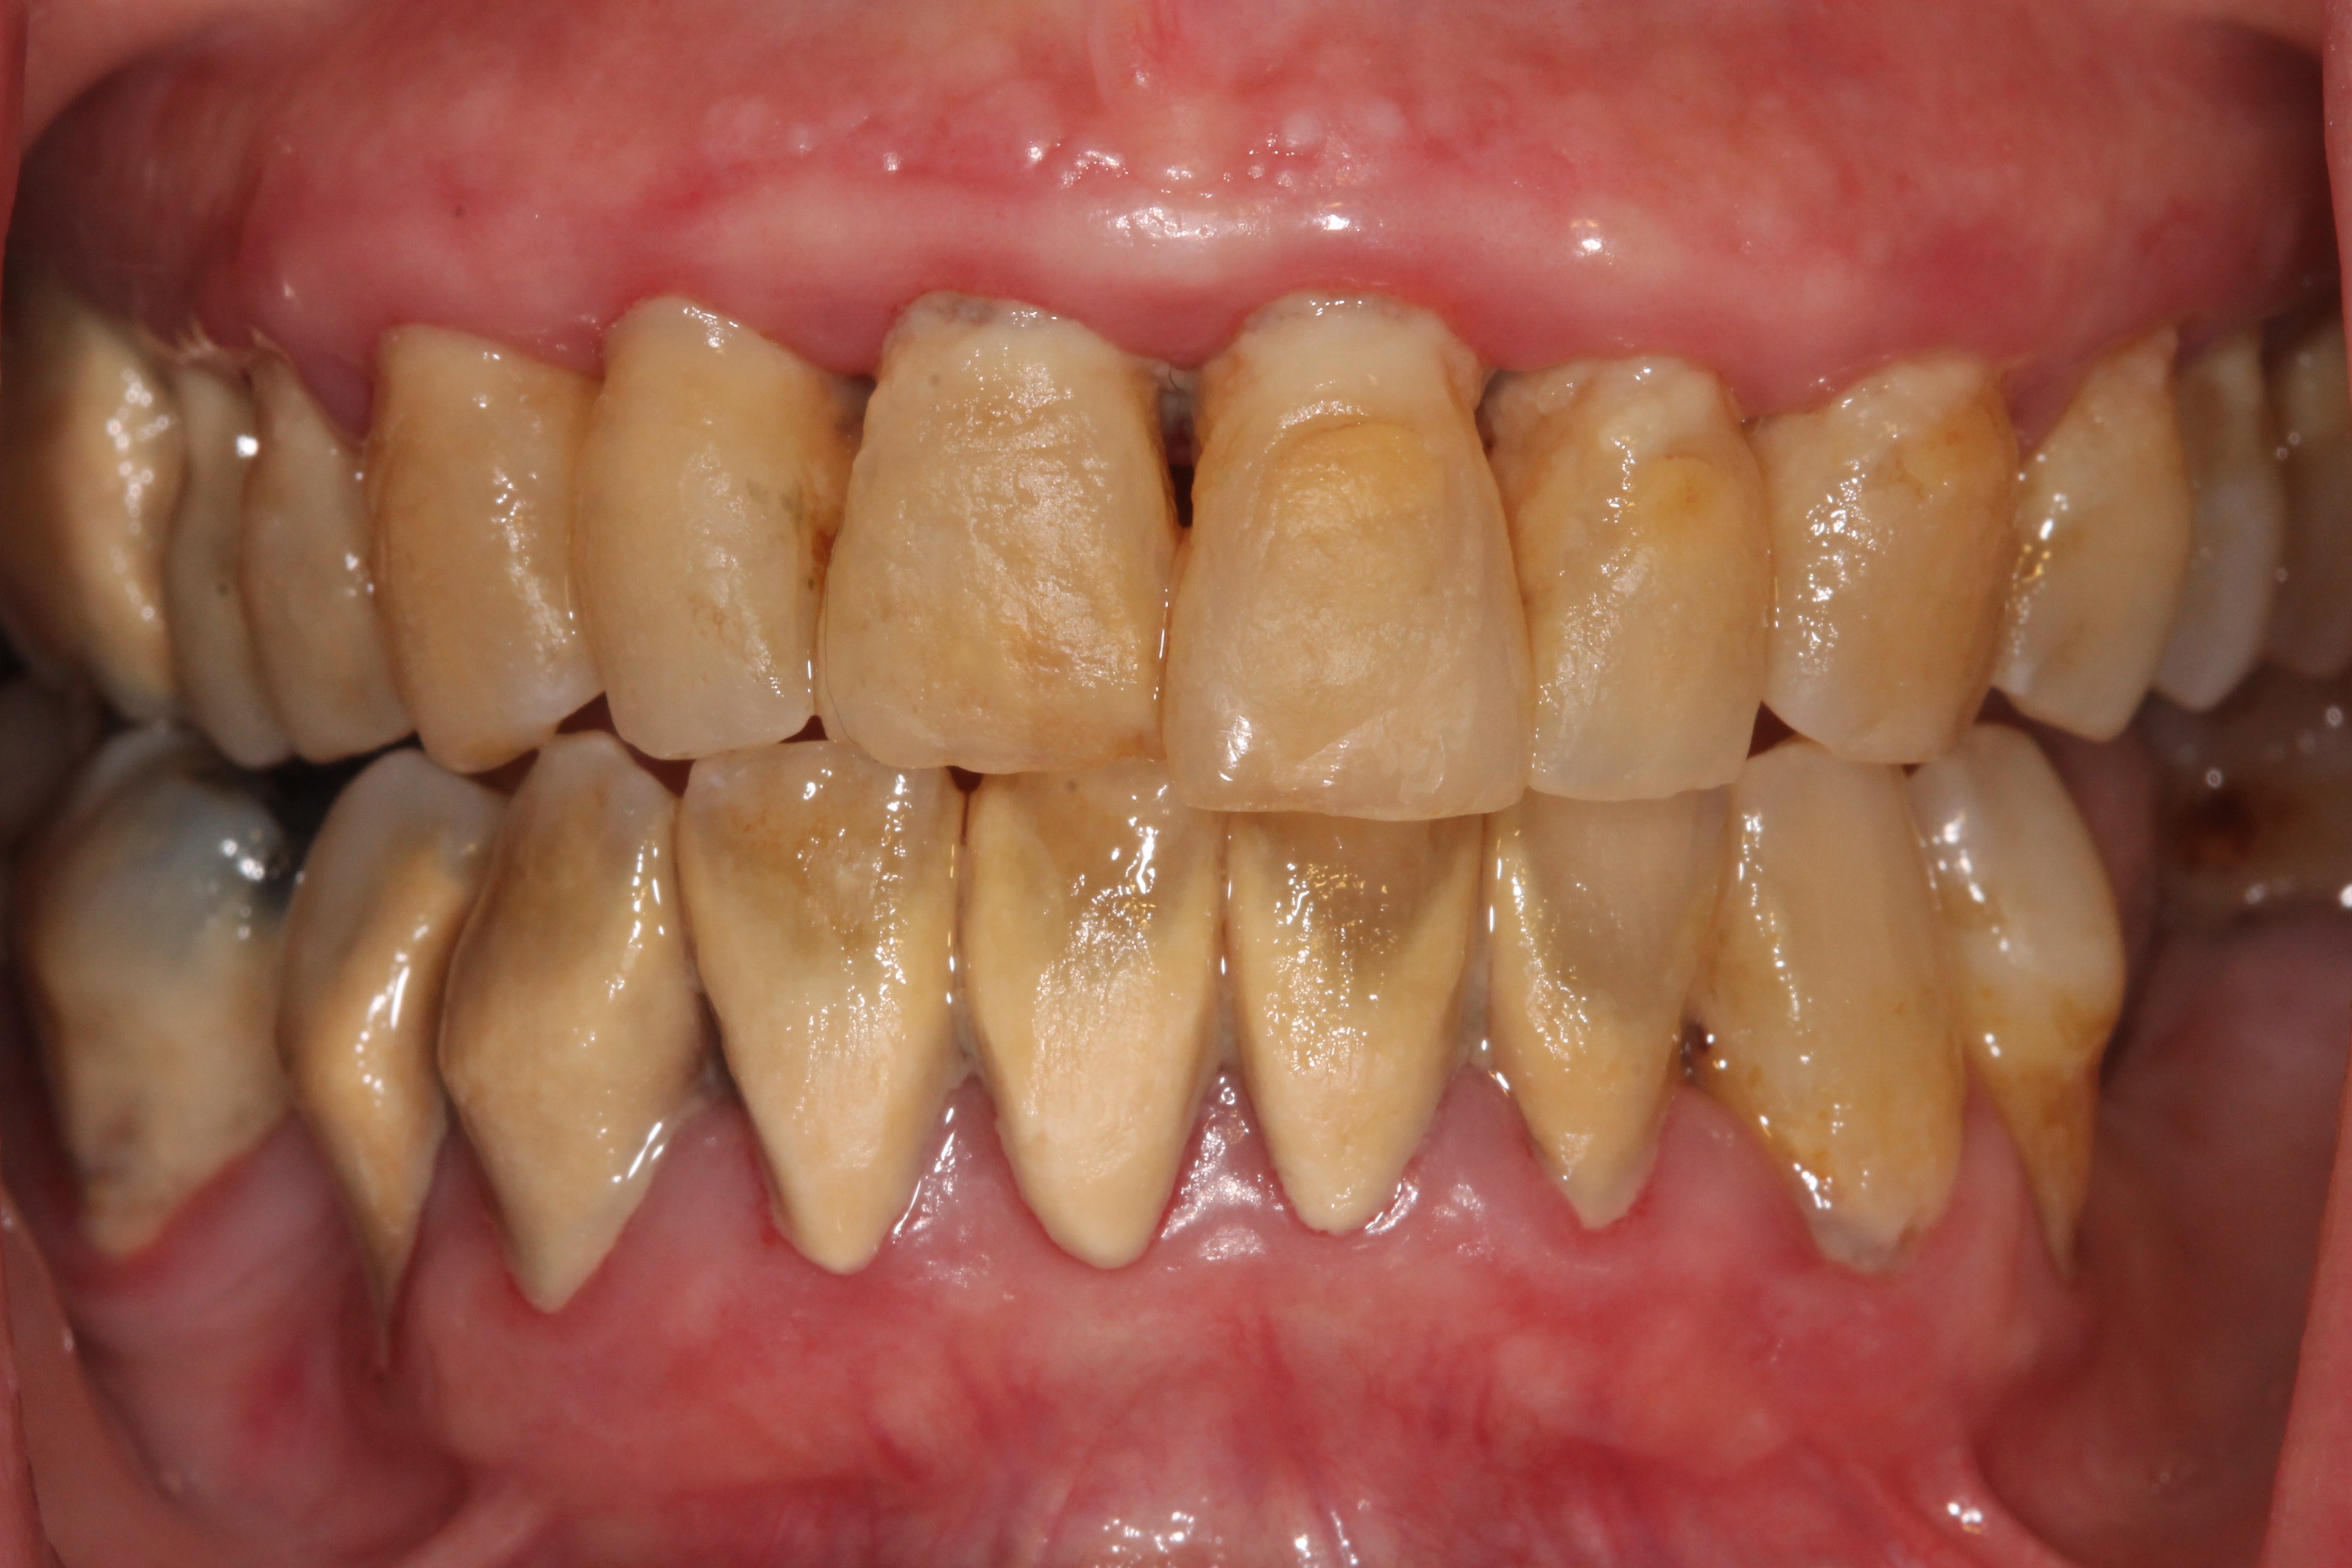

ΕΝΔΕΙΚΤΙΚΑ ΠΕΡΙΣΤΑΤΙΚΑ ΤΗΣ ΝΟΣΟΥ

προχωρημένο στάδιο

Περιοδοντίτιδα

Στην περιοδοντίτιδα η φλεγμονή από επιφανειακή που ήταν στην ουλίτιδα, επεκτείνεται βαθύτερα, προκαλεί αποκόλληση των ούλων από το δόντι, βάθυνση της ουλοδοντικής σχισμής, δημιουργία περιοδοντικών θυλάκων και σταδιακή καταστροφή του οστού που στηρίζει το δόντι.

Η σημαντική διαφορά μεταξύ ουλίτιδας και περιοδοντίτιδας είναι ότι στην περιοδοντίτιδα υπάρχει μόνιμη οστική καταστροφή, η οποία ποικίλει ανάλογα με την βαρύτητά της. Εάν η περιοδοντίτιδα δεν θεραπευθεί έγκαιρα ή εάν μετά τη θεραπεία παραμεληθεί η στοματική υγιεινή από τον ασθενή, η οστική καταστροφή επιδεινώνεται, το δόντι κινείται, είναι πιθανό να αλλάξει θέση, σταδιακά χάνει τη λειτουργικότητά του και συχνά καταλήγει σε εξαγωγή.